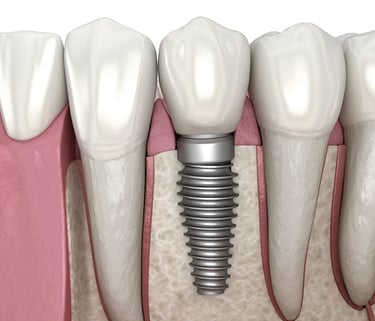

Dental implants are designed to provide a foundation for replacement teeth that look, feel and function like natural teeth. The person who has lost teeth regains the ability to eat virtually anything and can smile with confidence, knowing that teeth appear natural and that facial contours will be preserved. The implants are tiny titanium posts which are placed into the jaw bone where teeth are missing. The bone bonds with the titanium, creating a strong foundation for artificial teeth. In addition, dental implants can help preserve facial structure, preventing the bone deterioration which occurs when teeth are missing.

Dental implants are metal anchors, which act as tooth root substitutes. They are surgically placed into the jaw bone. Small posts are then attached to the implant, which protrude through the gums. These posts provide stable anchors for artificial replacement teeth.

For most patients, the placement of dental implants involves two surgical procedures. First, dental implants are placed within your jaw bone. For the first three to six months following surgery, the implants are beneath the surface of the gums, gradually bonding with the jaw bone. You should be able to wear temporary dentures and eat a soft diet during this time. At the same time, your restorative dentist designs the final bridgework or denture, which will ultimately improve both function and aesthetics.

After the dental implant has bonded to the jaw bone, the second phase begins. The surgeon will uncover the implants and attach a small healing collar. Dr. Prasad and Dr. Siddhi can then start making your new teeth. An impression must be taken. Then posts or attachments can be connected to the implants. The replacement teeth are then made over the posts or attachments. The entire procedure usually takes 3 to 6 months. Most patients do not experience any disruption in their daily life.